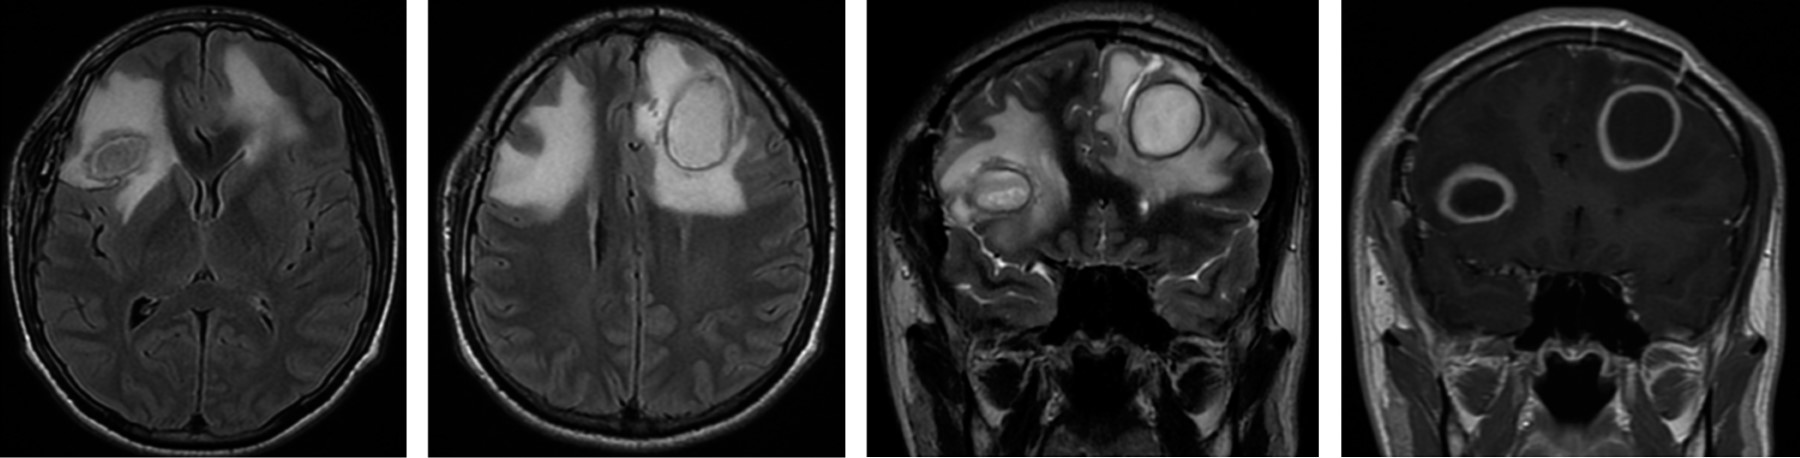

Absceso cerebral bilateral frontal, medicina hiperbárica, cirugía y terapia antimicrobiana en germen extraño. Reporte de caso y revisión de la literatura

El absceso cerebral es un evento extraño en el paciente inmunológicamente competente, por lo general secundario a procesos infecciosos en cavidades craneales, principalmente en senos paranasales, celdillas mastoideas y oído medio. Diferentes esquemas de manejo han sido propuestos en presencia de microorganismos que día a día son más resistentes a los tratamientos farmacológicos. Dependiendo del tamaño y la localización, los abscesos cerebrales requieren tratamiento médico y quirúrgico en conjunto con técnicas modernas como la terapia hiperbárica. Presentamos un caso clínico de un hombre de 20 años con cefalea intensa y compromiso del estado neurológico secundario a dos abscesos en lóbulos frontales con erradicación del 100% de las colecciones y mejoría del estado neurológico y funcional del paciente.

Figura 1